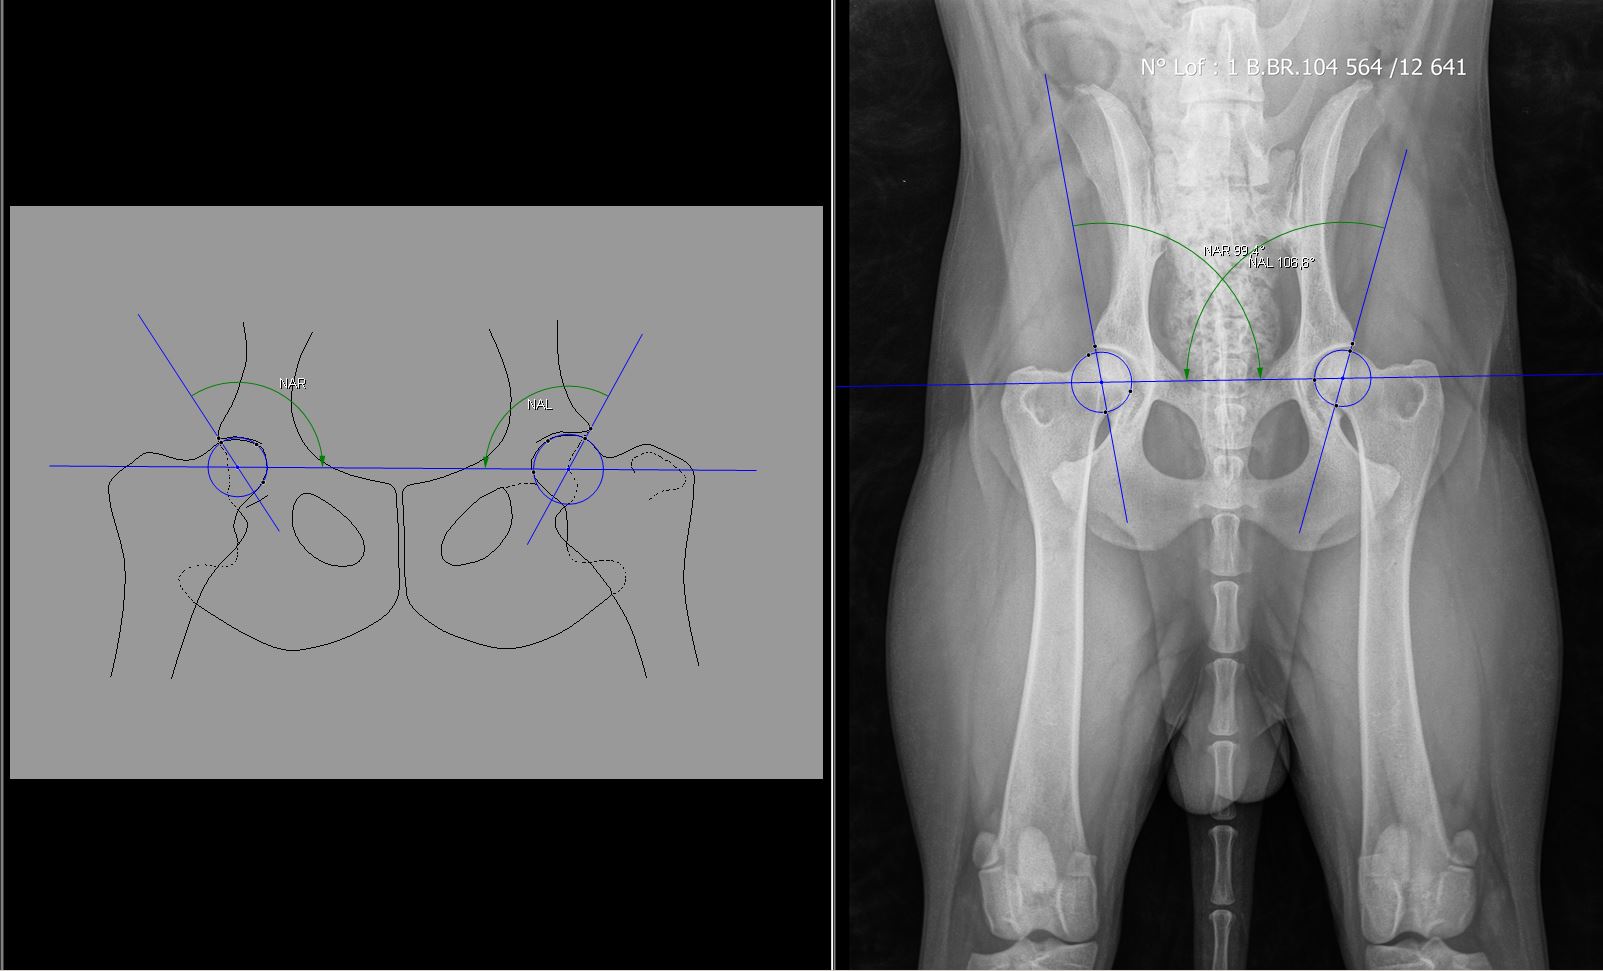

Radiologie Equine

Pour les vétérinaires équins, Vet X propose des équipements vétérinaires spécifiques en imagerie (radiologie, échographie), chirurgie et thérapie afin de vous faciliter la vie, d’optimiser votre temps et d’accélérer le rétablissement de l’animal tout en augmentant son bien-être et la satisfaction de son maître.